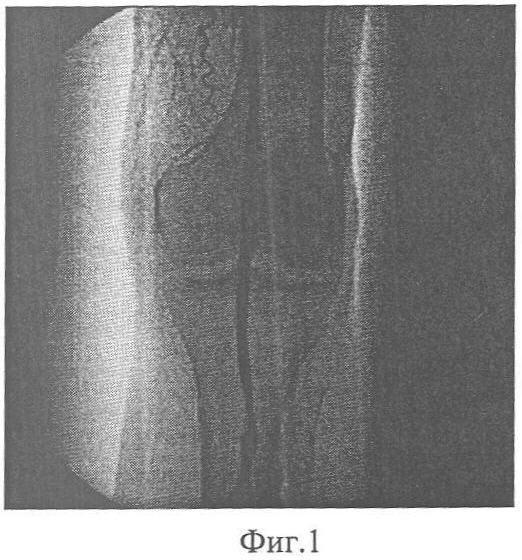

Фиг.3 – ангиограмма конечности больного П. после тромбэктомии и туннелизации конечности;

Выполнена диагностическая артериография левой нижней конечности. На артериограмме определяется окклюзия левой подколенной артерии в средней порции. Дистальнее контрастируется подколенная артерия с начальными отделами берцовых артерий. Средняя треть голени и стопа аваскулярны (Фиг.1, 2).

Для компенсации кровообращения конечности больному выполнена операция – непрямая тромбэктомия из левой подколенной и задней большеберцовой артерии до ее средней трети, туннелизация метафизов и диафиза левой большеберцовой и пяточной костей.